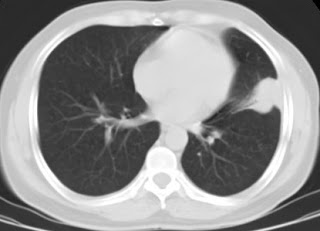

Haematogenic secondary spread of a primary lung tumor (adenocarcinoma)。Lesions should be punctured peripherically targeting it’s wall.